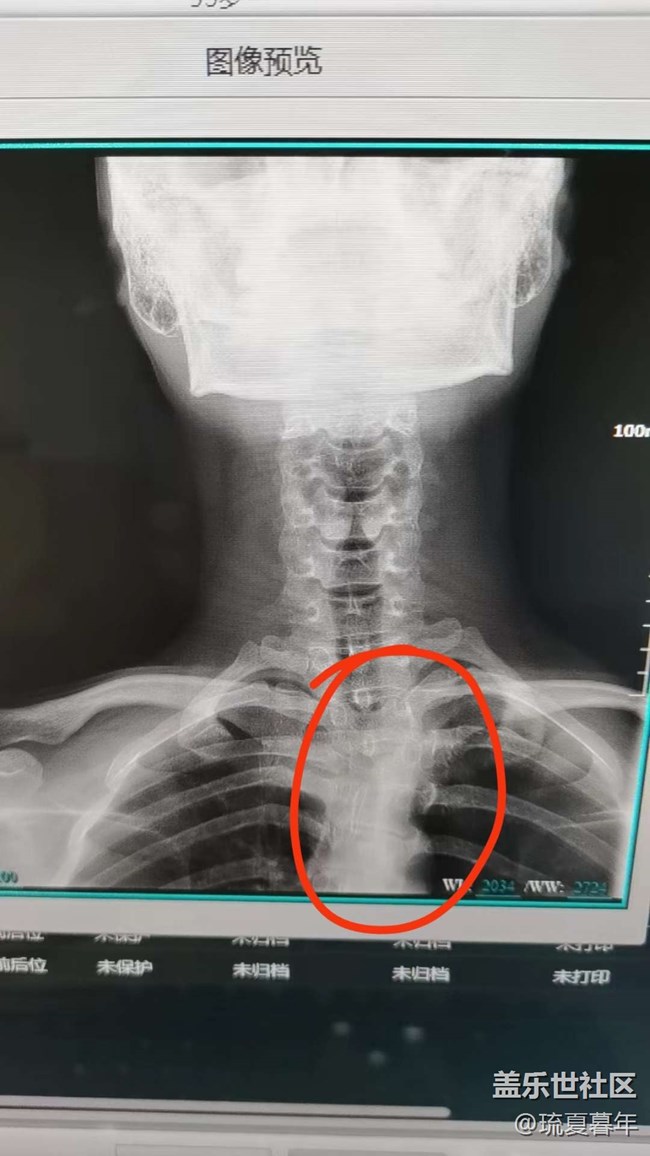

有一點點脊柱側彎 圖片

但是問題不大,屬于生理性的,大家平時注意